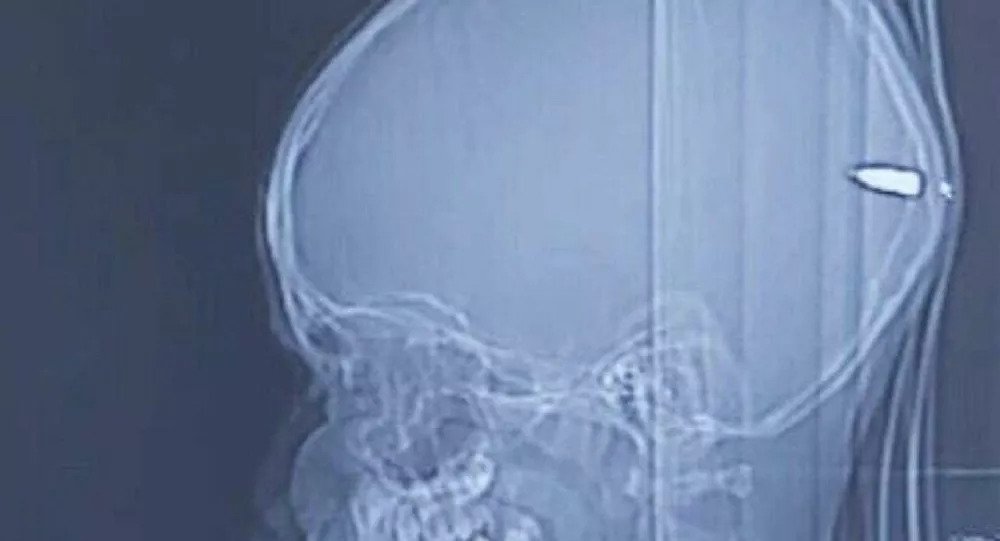

Αντιμέτωποι με ένα απίστευτο εύρημα οι ιατροί, καθώς βρήκαν μια σφαίρα 9 χιλιοστών καρφωμένη στον εγκέφαλο ενός 9χρονου αγοριού.

Σε διαδικασία ανάρρωσης βρίσκεται ένας 9χρονος από την Ανατολική Ιερουσαλήμ μετά την χειρουργική επέμβαση στην οποία υποβλήθηκε στο Ιατρικό Κέντρο Χαντάσα για την αφαίρεση μιας σφαίρας που είχε καρφωθεί στον εγκέφαλό του. Η σφαίρα των 9 χιλιοστών διαπέρασε τον εγκέφαλο του αγοριού, σταμάτησε στο εσωτερικό του κρανίου και καρφώθηκε τελικά μέσα στον εγκέφαλο.

Οι γονείς του μικρού, από την παλαιστινιακή γειτονιά του Ρας αλ Αμούντ, πήγαν τον 9χρονο στο νοσοκομείο το βράδυ της Παρασκευής, καθώς εμφάνιζε υπνηλία και είχε ένα μικρό τραύμα στο κεφάλι και ίχνη αίματος στα μαλλιά του. Οι γιατροί έμειναν άναυδοι όταν είδαν στην αξονική τομογραφία μία σφαίρα στο κεφάλι του παιδιού.

Ο νευροχειρουργός Γκάι Ελόρ δήλωσε «έκθαμβος» στην εφημερίδα «The Times of Israel», καθώς όπως τόνισε, παρότι η σφαίρα διαπέρασε «πολύ σημαντικές εγκεφαλικής δομές», το αγόρι μιλάει και αναρρώνει, χωρίς να έχει υποστεί καμία εγκεφαλική ζημιά.

Όταν το παιδί στάλθηκε στον αξονικό τομογράφο, ο Ελόρ επέστρεφε στο σπίτι του για το δείπνο του Σαββάτου με την οικογένειά του. Του τηλεφώνησαν από το νοσοκομείο και του είπαν ότι «η αξονική τομογραφία έδειξε ότι μια σφαίρα διαπέρασε την δεξιά πλευρά του κρανίου, πέρασε μέσα από τον εγκέφαλο και σταμάτησε στο πίσω μέρος του κεφαλιού».

«Αφού σταθεροποιήσαμε το παιδί, μπήκαμε στο χειρουργείο και προσπαθήσαμε να εντοπ΄σιουμε τη σφαίρα που είδαμε στην αξονική τομογραφία. Προς έκπληξή μας δεν ήταν εκεί. Χρειάστηκε να χρησιμοποιήσουμε κάποια τεχνολογία τελευταίας τεχνολογίας για να διαπιστώσουμε ότι η σφαίρα είχε επιστρέψει στο αριστερό μέρος του εγκεφάλου» επισήμανε ο Ελόρ και σχολίασε: